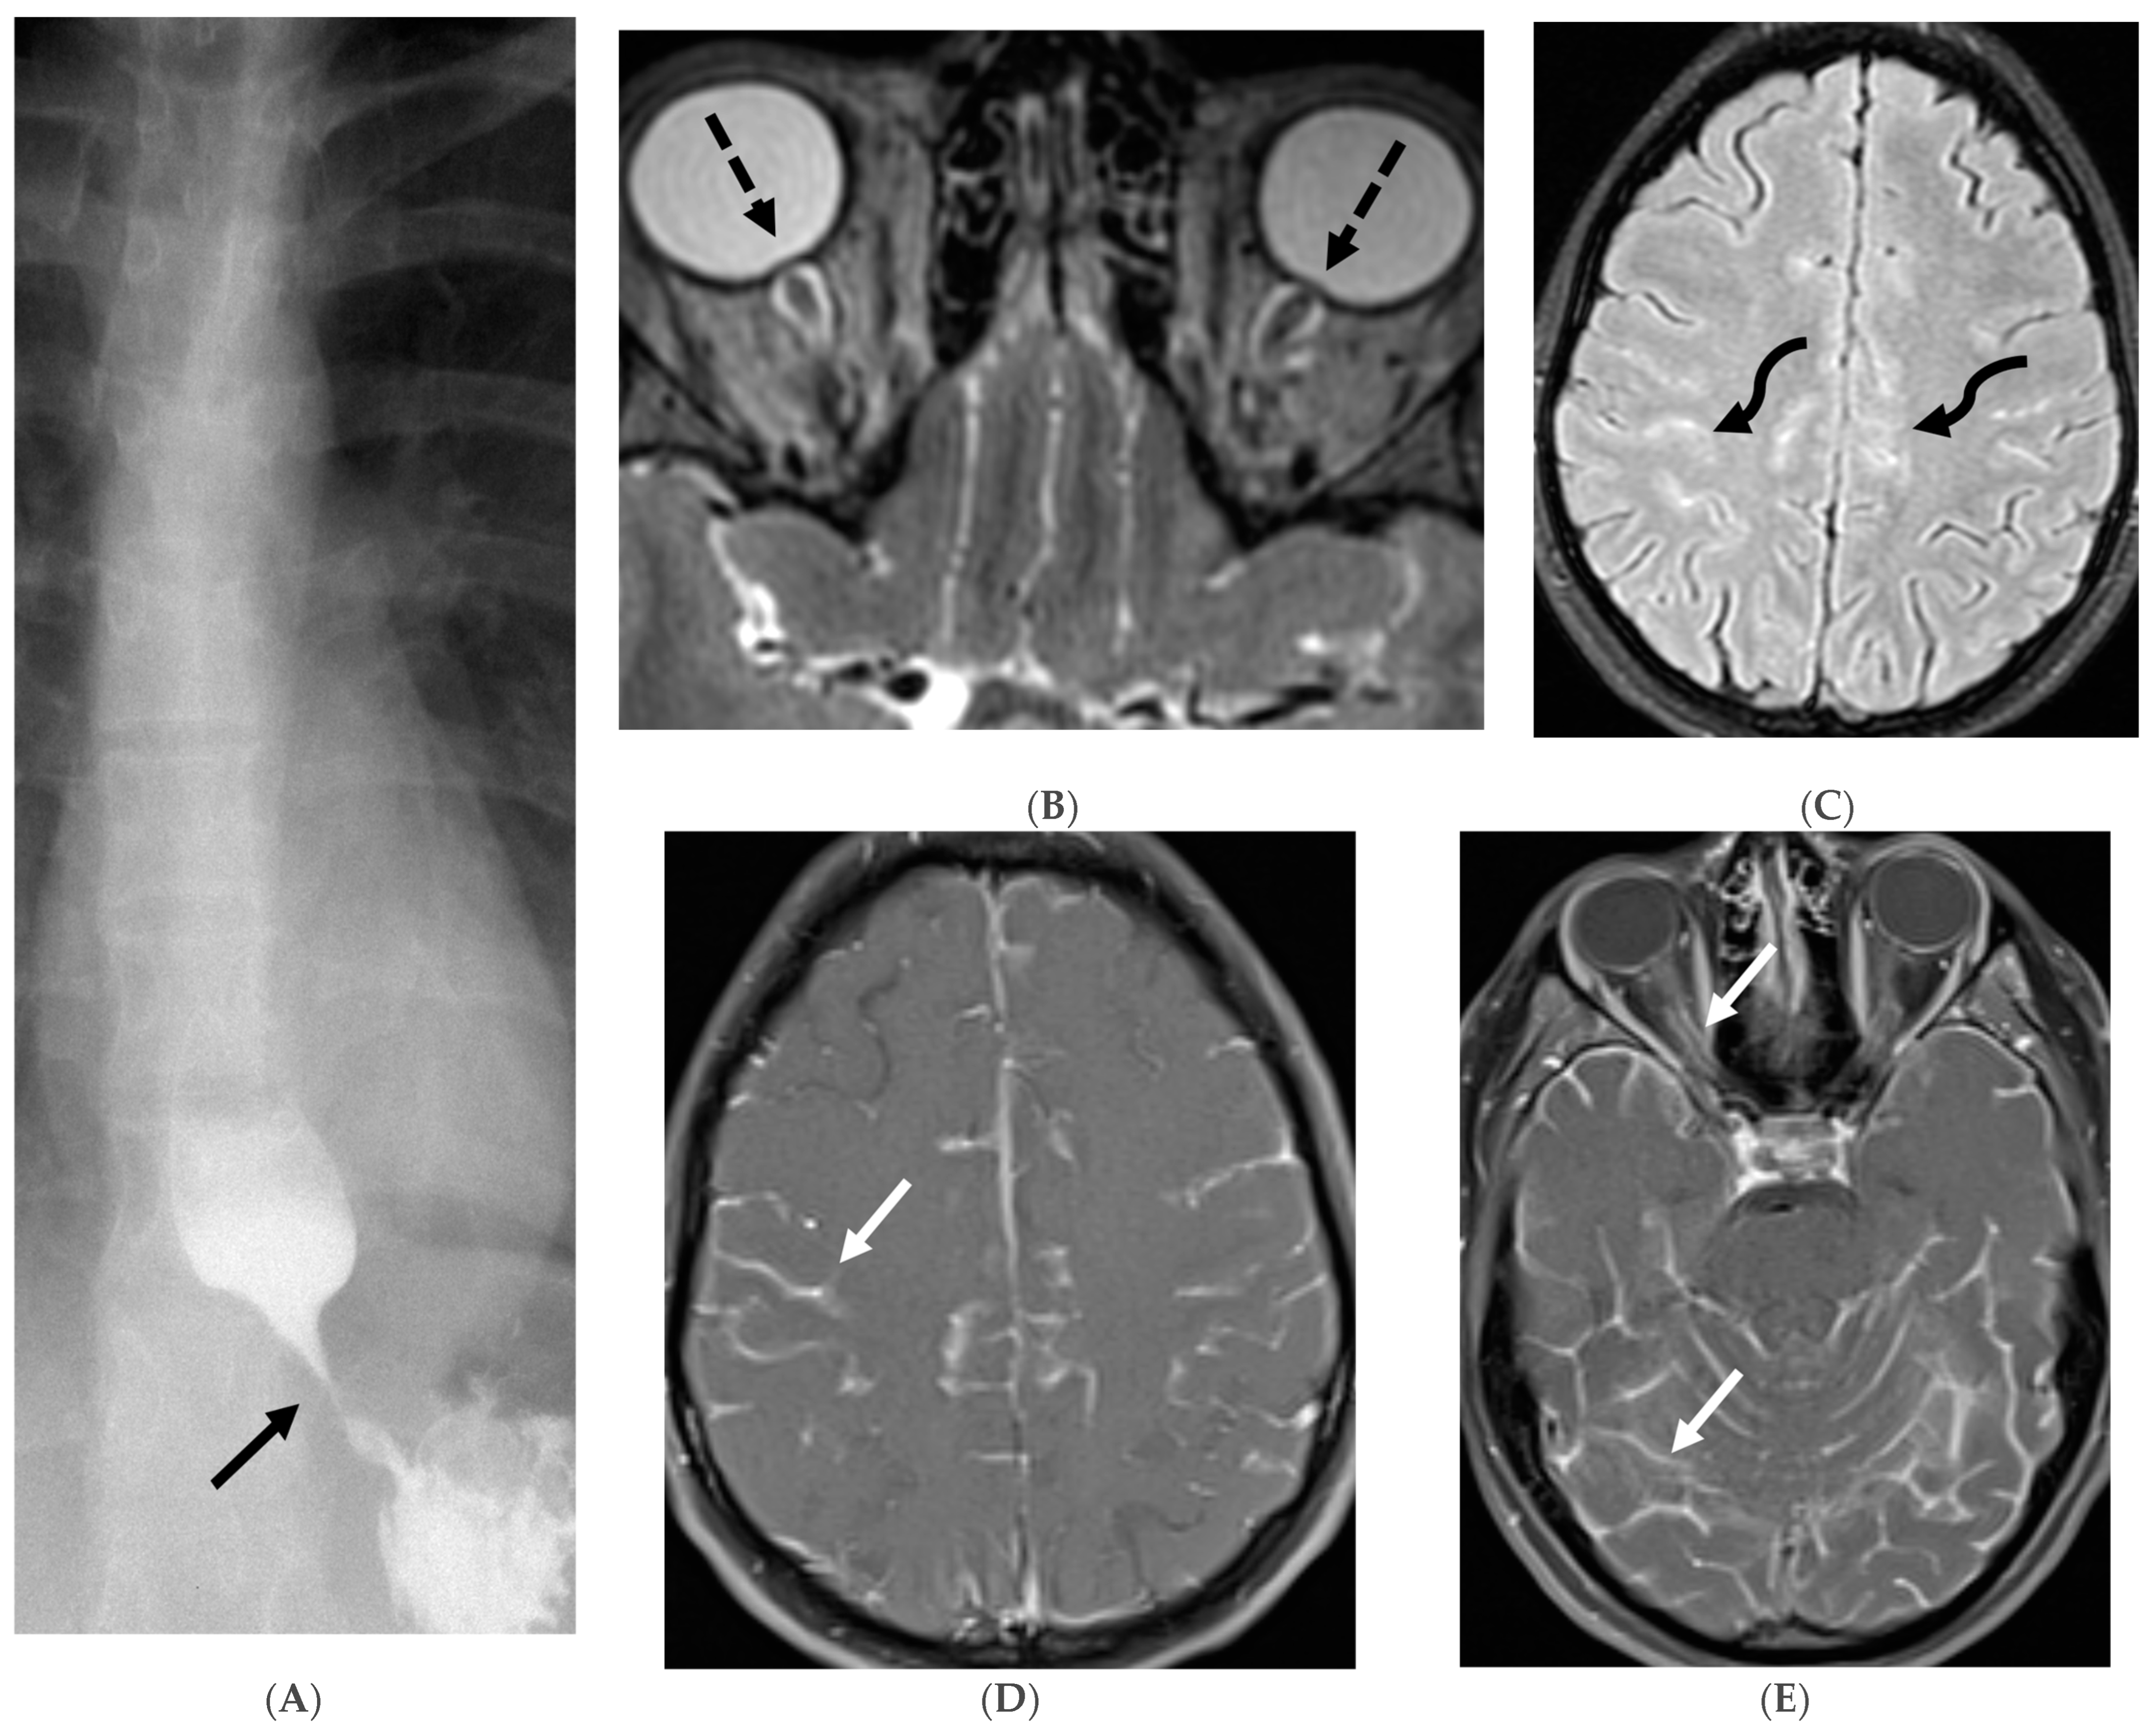

The typical MRI presentation of SMM involves serpentine, nodular, or plaque-like enhancement in sulcal spaces, basal cisterns and along the cauda equina nerve roots [87,88]. Notably, SMM enhancement on post contrast [PC]-T1 images is superior to the PC-FLAIR in contrast to that seen in infectious meningitis [84]. However, in case of a non-enhancing primary tumor, FLAIR and DWI are important sequences to look for SMM. Hydrocephalus and subependymal deposits are other common features found in kids with SMM (Figure 15, Figure 16 and Figure 17). Positive cytology on CSF analysis, especially with leukemia, is important [89].

Figure 15.

Axial DWI (A), axial ADC (B), axial T1 FS post contrast (C) and Fluorodeoxyglucose Positron Emission Tomography (FDG–PET) scan (D): 13-year-old male with bilateral leg pains, headache, fever and weight loss: Blood tests and CT scan were concerning for Burkitt’s lymphoma. There is heterogeneous calvarial bone marrow signal with restricted diffusion (arrows) and patchy enhancement (curved arrows). Diffuse thickening and enhancement of pachymeninges in the supratentorial compartment is noted (dashed arrows). Findings are most consistent with lymphomatous involvement. Multifocal diffuse/heterogeneous pattern of FDG uptake within the axial and appendicular skeleton and the calvarium (open arrows). Intense FDG avid uptake is seen in the presacral mass (star).

Figure 16.

16-year-old female with 4 months history of globus sensation and recent botox injection of lower esophageal junction. Headache and vomiting for past week: Esophagogram (A), Axial T2 orbits (B), axial FLAIR (C) and post contrast T1 (D,E): Narrowing of the Gastroesophageal (GE) junction with beaked configuration and mild distention of the lower esophagus likely from early achalasia (black arrow). There is bilateral papilledema indicating raised ICP (dashed arrows) and sulcal hyperintensity (curved black arrows). Diffuse LME in the supra-and-infratentorial regions and along optic sheaths raising the concern for leptomeningeal carcinomatosis (white arrows). Pathology: Gastric adenocarcinoma metastasis.

Figure 17.

Axial T2 FS (A), axial Susceptibility weighted imaging (SWI) (B), axial DWI (C), post contrast sagittal and axial T1 post contrast (D,E): 19-year-old female with history of stage IV neuroblastoma, left paraspinal primary ganglioneuroblastoma, treated with chemotherapy, radiation and bone marrow transplant presents with headache. There are extensive hemorrhagic leptomeningeal masses, both supra and infratentorial region (arrows). The lesions also demonstrate restricted diffusion which could be secondary to internal hemorrhage or high cellularity of the tumor(curved arrows). The larger masses invade the cortex of both cerebral hemispheres, with surrounding vasogenic edema (black arrow). Avid enhancement of the lesions is seen along with overlying dura (dashed arrows). Features are in keeping with extensive leptomeningeal metastatic neuroblastoma.